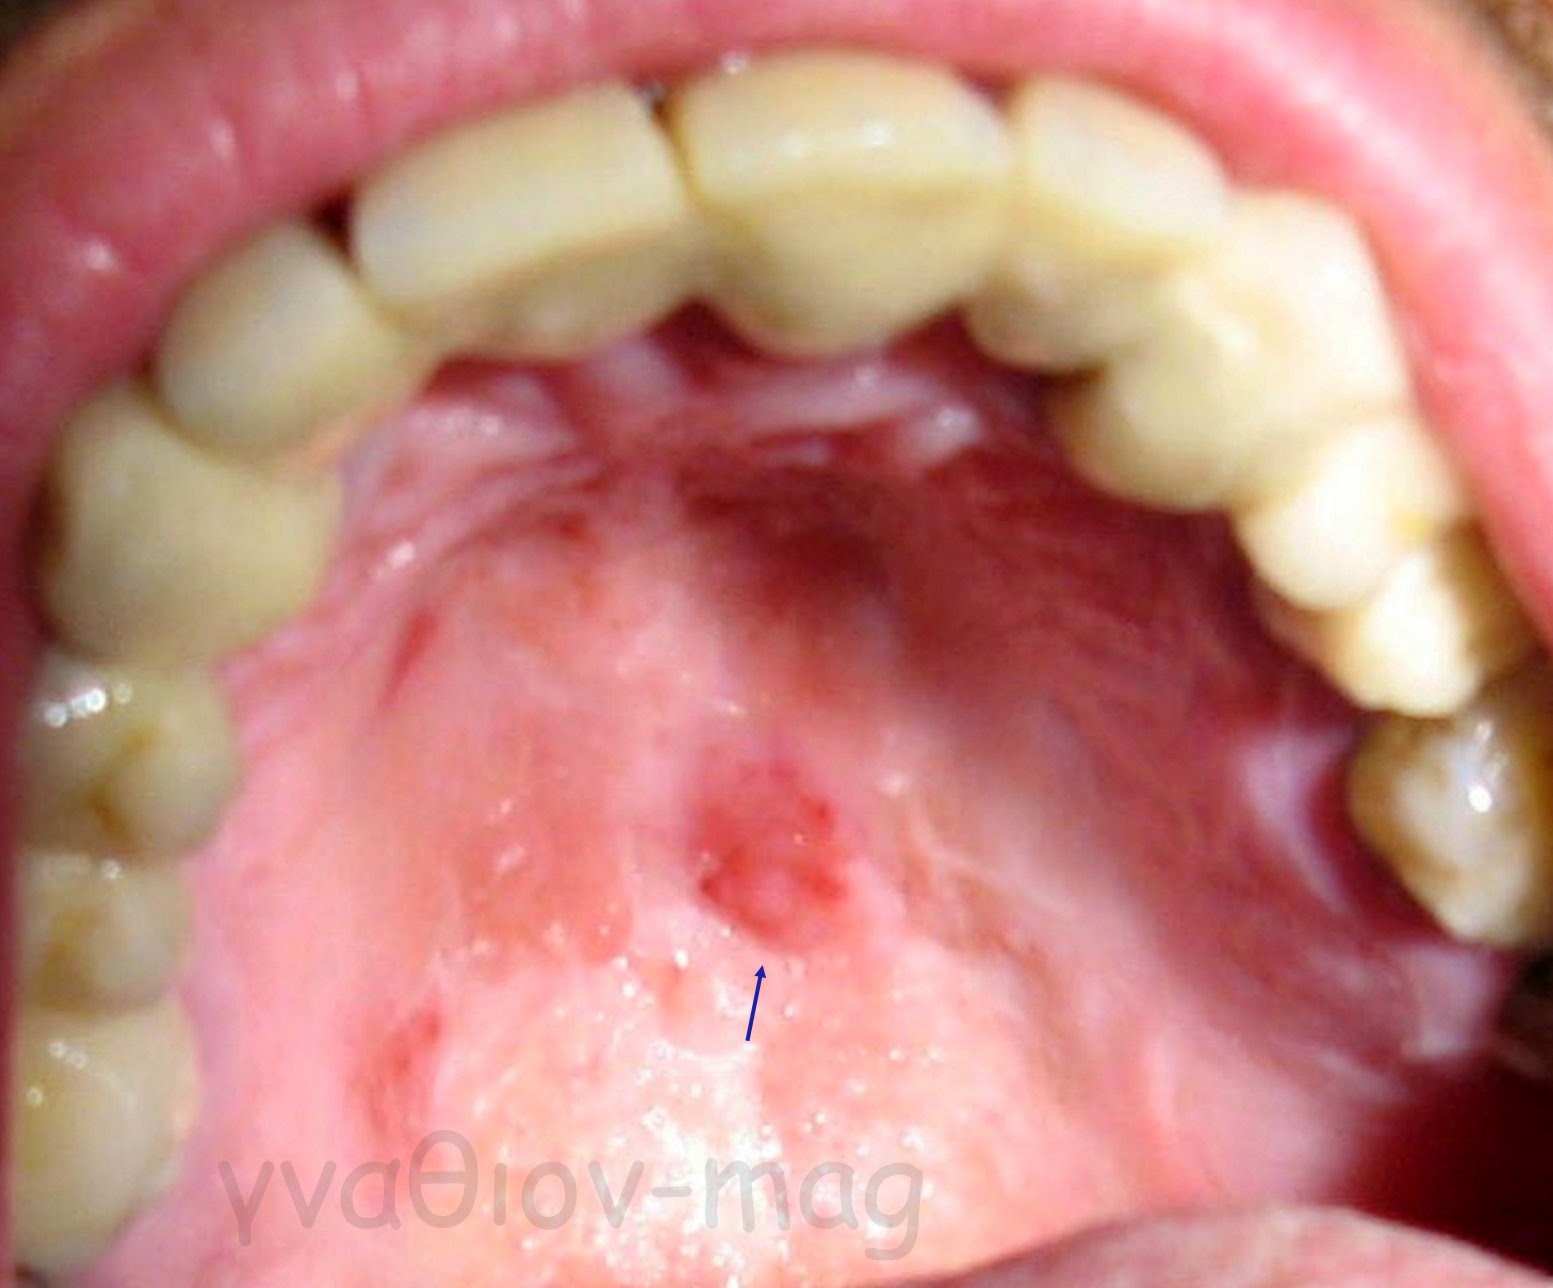

Ωστόσο, σαν γενική αρχή, αν μια βλάβη παραμένει στο στόμα περισσότερο από μία εβδομάδα χωρίς σημεία ύφεσης, ακόμη κι αν είναι ανώδυνη, θα πρέπει να εξετάζεται από ειδικό γιατρό (Εικόνα 2).

Εικόνα 2. Εμμένουσα ερυθρή βλάβη στην υπερώα (βέλος)